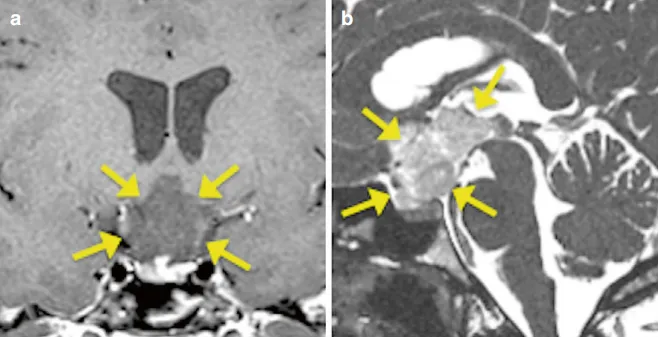

MRI显示,她的视路-下丘脑区域长了一个巨大的胶质瘤,肿瘤已深深侵入第三脑室。

从无法手术,到全切肿瘤,妮娜找到巴教授。巴教授通过额间纵裂入路,将肿瘤完全切除。术后病理证实是毛细胞型星形细胞瘤,这是一种全切便有望长期生存的胶质瘤。